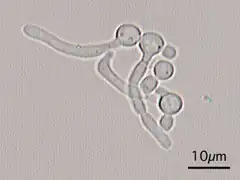

| 1:pseudohyfen, 2:chlamydospore, 3:blastspore, 4:gistachtige cellen | ||||||||||||